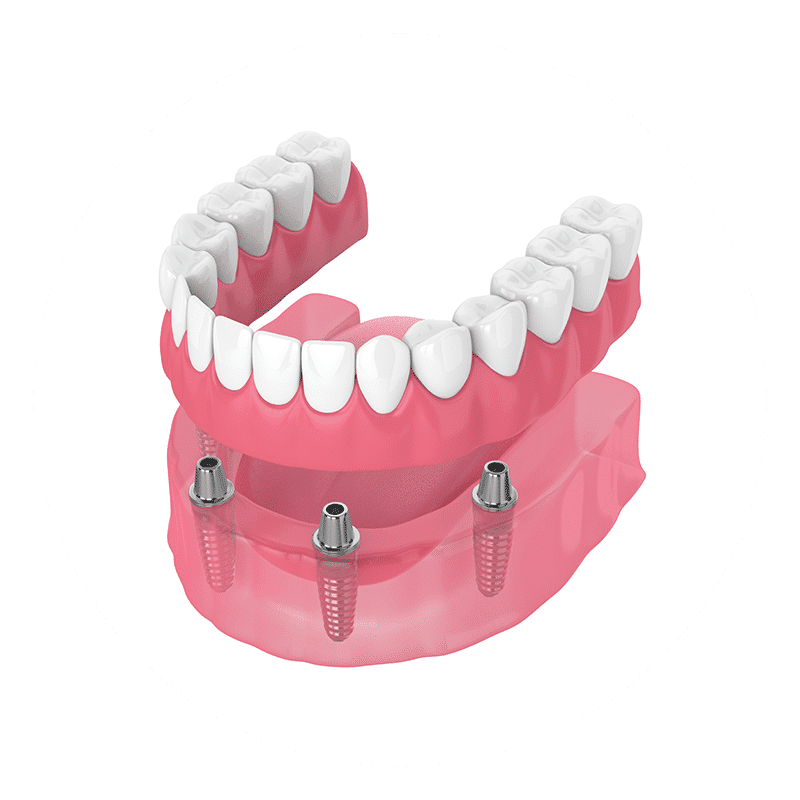

Full Set of Teeth

There are several options for cases in which a full arch is missing. Dental implant bridges can work well, and for this, we would usually recommend the excellent All-on-4 technique.